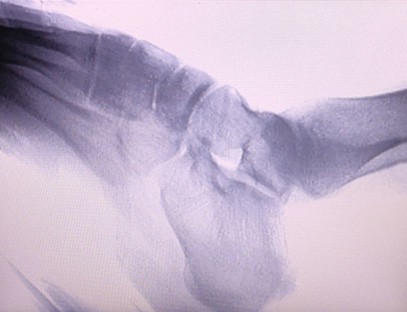

Una máquina de rayos X portátiles un instrumento portátil de baja dosis de radiación, muy seguro, que puede obtener imágenes de alta calidad al tiempo que reduce la exposición a la radiación. Compensa las deficiencias de los grandes equipos hospitalarios y se puede mover y transportar en cualquier momento. Especialmente adecuado para unidades e individuos con presupuesto insuficiente y bajos requisitos de imágenes. Nuestra máquina de rayos X de nueva generación está equipada con una pantalla grande de alta definición de 10 pulgadas, que tiene un rango de ángulo de visión más amplio y puede ver completamente a través de toda la palma, incluidas fracturas, dislocaciones, artritis y tumores óseos. Se puede conectar a una impresora de películas para imprimir películas ortopédicas y también se puede utilizar para producción y pruebas industriales. No necesita un cuarto oscuro, perspectiva directa, observación en tiempo real. Esta máquina tiene un sistema de imágenes de alta resolución que puede capturar imágenes de cualquier estructura ósea con mucha claridad. Proporcionar los mejores equipos y soluciones de prueba de rayos X para fabricantes de productos médicos, de mascotas, industriales, electrónicos, departamentos de inspección y mantenimiento y laboratorios de investigación.

Especialización:Diseñado para las necesidades de las clínicas ortopédicas, especialmente adecuado paraImágenes de rayos Xde extremidades como manos, muñecas, codos, hombros, rodillas, tobillos, etc.

Imágenes claras:Se utiliza tecnología avanzada de imágenes digitales para proporcionar imágenes de rayos X de alta calidad, lo que ayuda a los médicos a diagnosticar la afección con precisión.